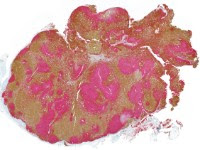

3. CD3 (marrón) – CD20 (rojo) 2x

• Histológicamente se observa una tríada característica (también conocida como linfadenitis de Piringer-Kuchinka): un patrón de hiperplasia folicular con centros germinales reactivos, histiocitos epitelioides perifoliculares (ocasionalmente formando agregados en forma de microgranulomas e invadiendo los folículos) y una expansión paracortical de células B de aspecto monocitoide.

• Los nevus melanocíticos ganglionares son inclusiones benignas de células melanocíticas localizadas en la cápsula o trabéculas del ganglio, sin atipia ni actividad mitótica. Se consideran hallazgos incidentales sin relevancia clínica.

• Pueden simular metástasis de melanoma, pero su localización periférica y ausencia de rasgos atípicos permiten diferenciarlos. La inmunohistoquímica (S100+, Melan-A+, HMB45+) confirma su naturaleza melanocítica.